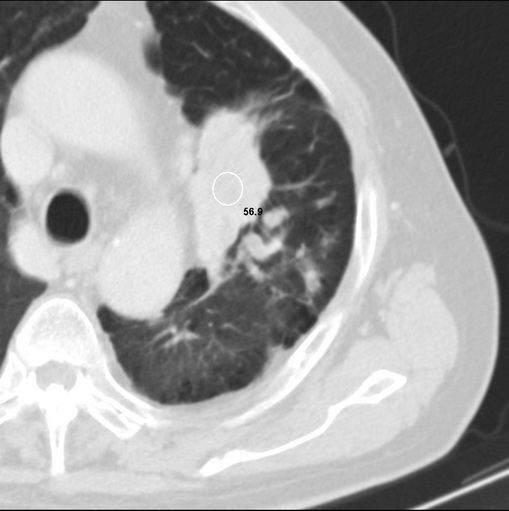

标题: CT25434:胸部CT增强扫描

男性患者 81岁 咳嗽 咳痰 咯血

左肺中心型肺癌并:1.左肺阻塞性肺炎;2.纵隔淋巴结肿大;

考虑左上肺癌并阻塞性肺炎,左肺转移、左肺门及纵隔淋巴结转移。

肿块贴近左肺门,包绕左上肺动脉,形态不规则。肿块增强扫描中度强化。纵膈内主动脉弓左旁间隙、气管隆突前、下间隙见多枚淋巴结影。综上考虑左侧中央型肺癌可能性大。图片没有完整上传,尤其是左肺上叶支气管分支层面没有上传,因此不好判断是叶支气管中断还是段支气管中断。另外,下图红色部分所示是“黏液支气管征”吗?